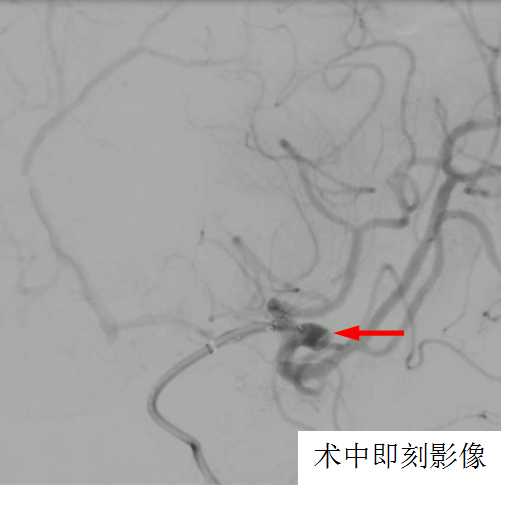

经过详细告知和沟通,家属知情同意后,术前准备充分,在影像介入室、麻醉科的全力配合下,团队于5月14日在全麻下为患者施行了大脑中动脉瘤内扰流装置WEB植入术,手术顺利,仅用时15分钟就完成了WEB植入,术中即刻造影显示动脉瘤内造影剂滞留明显,其余左侧大脑中动脉M1段、M2上干及下干等血管均通畅。患者术后顺利苏醒,拔管后无特殊不适,言语功能及肢体功能未受影响。